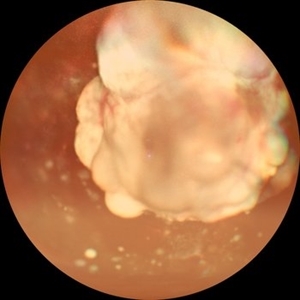

Retinoblastoma

Wide-field color fundus photograph of a 2-month old female with retinoblastoma.

Photographer: Dr. Akansha Sharma-Retina Foundation, Ahmedabad

Condition/keywords: RB gene mutation, retinoblastoma